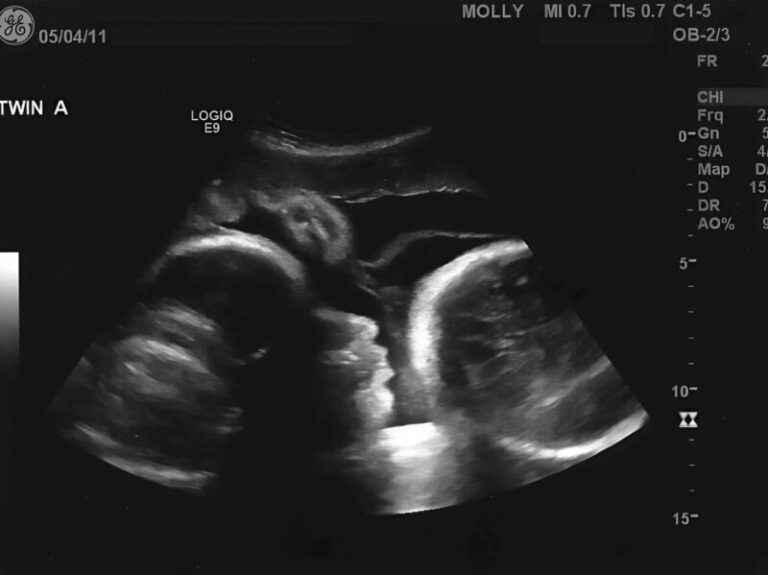

In this illustrative case, a 66-year-old woman began experiencing persistent abdominal discomfort…